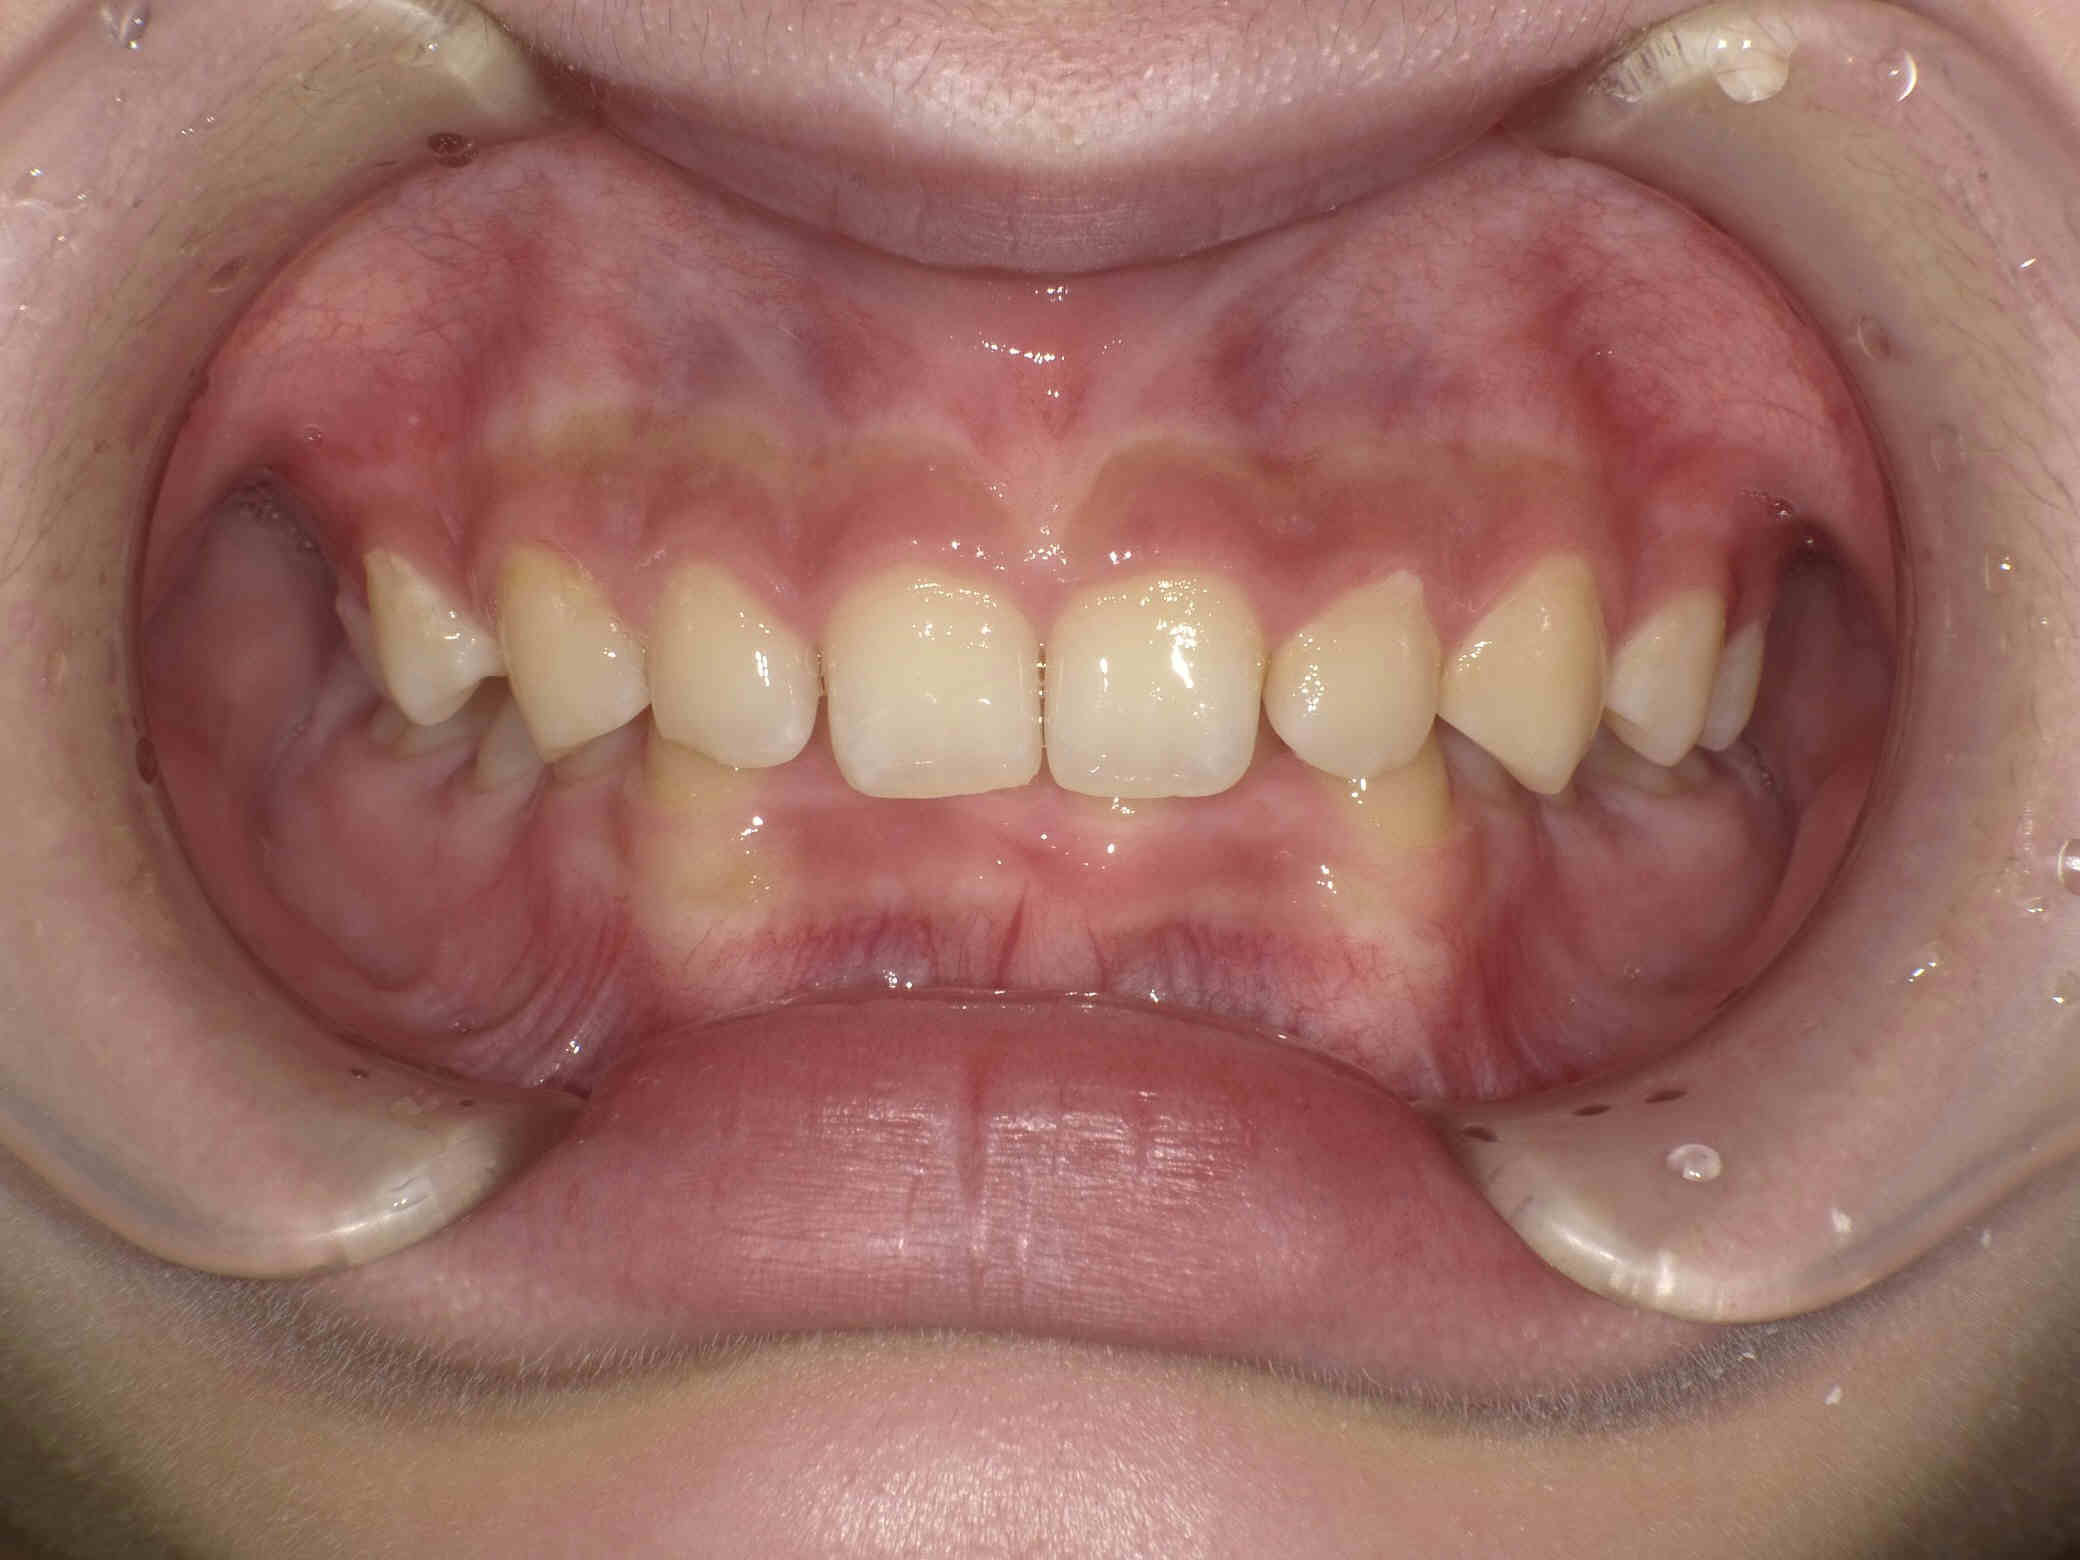

• 治療前

12歳6ヶ月〜スタートです。

やや出っ歯傾向で、噛み合わせが深く

歯並びがデコボコな鋏上咬合(はさみじょうこうごう)という状況でした。

上下の歯がすれ違っている状態で、一部の歯に過度の負担がかかってしまいます。